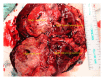

A 22-year-old female presented with back pain and was discovered to have a right-sided abdominal mass. Computed tomography (CT) scan revealed a 9 cm enhancing right upper pole renal mass with suspicion for tumor thrombus into the right renal vein and possibly the inferior vena cava (IVC). Magnetic resonance imaging (MRI) confirmed tumor thrombus into the inferior vena cava approximately 3 cm below the hepatic venous confluence. Open right radical nephrectomy with inferior vena cava thrombectomy was performed with removal of right kidney and tumor thrombus en bloc. Pathology revealed malignant epithelioid angiomyolipoma (EAML or PEComa). Epithelioid angiomyolipoma is a rare tumor of mesenchymal tissue that has the potential for local invasion and disease progression. Diagnosis of EAML was confirmed by pathology and immunohistochemistry. She was referred to medical oncology for discussion of surveillance versus potential adjuvant therapy and ultimately opted for close surveillance.